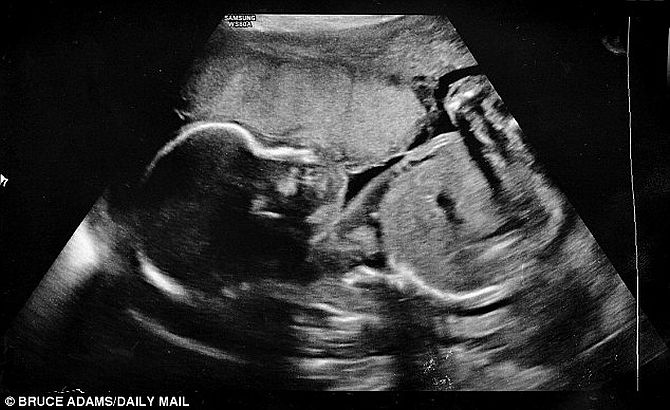

Αυτά τα λόγια δυστυχώς άκουσε η Louise Adams και ο σύζυγός της Jakk, την 22η εβδομάδα κύησης, όταν ξαφνικά έσπασαν τα νερά της.  Οι γιατροί ήταν κατηγορηματικοί…το μωράκι τους είχε το πολύ 5% πιθανότητες να ζήσει.

Η Louise όμως είχε άλλη άποψη.  Ενώ οι γιατροί, μην μπορώντας να κάνουν κάτι παραπάνω, απλά περίμεναν πότε θα αποβάλει, εκείνη ένιωθε το μωρό της μέσα στην κοιλιά να κλωτσάει.  Έτσι πήρε την απόφαση να μην το βάλει κάτω και πάση θυσία να σώσει το μωρό της.